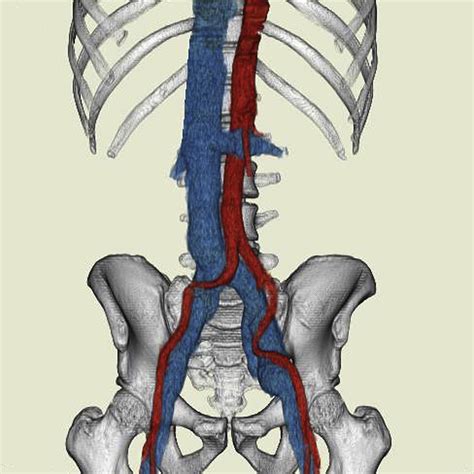

Inferior Vena Cava Dilatation occurs when the inferior vena cava, which runs from the lower extremities and abdomen to the heart, becomes dilated or enlarged. This enlargement can be caused by various factors, including increased pressure within the vein, blood clots, or underlying cardiovascular diseases. The inferior vena cava plays a critical role in the circulatory system, and any disruption in its function can lead to serious health complications.

• CT Scan: A computed tomography (CT) scan provides detailed images of the veins and can help identify the cause of dilation.